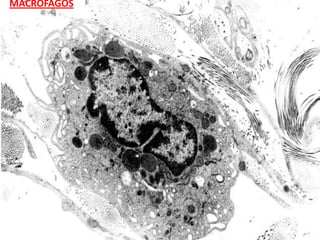

MACRÓFAGOS

CÉLULAS EMIGRANTES

- MACRÓFAGOS

CÉLULAS QUE      - MASTOCITOS O CÉLULAS CEBADAS

PARTICIPAN EN LA   - PLASMOCITOS O CÉLULAS PLASMÁTICAS

DEFENSA        - LEUCOCITOS:

NEUTRÓFILO, EOSINÓFILOS, LINFOCITOS.